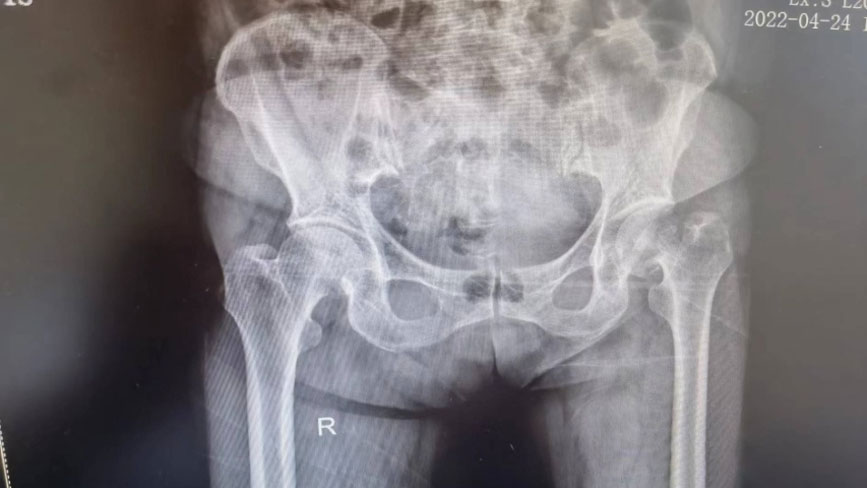

72岁的向奶奶因左侧股骨颈骨折,不能下床活动,已无法正常生活。面对日益恶化的病情,向奶奶来到来凤县人民医院骨伤科检查治疗。经检查,向奶奶的病情确诊为“左侧股骨颈骨折”。

术前图片